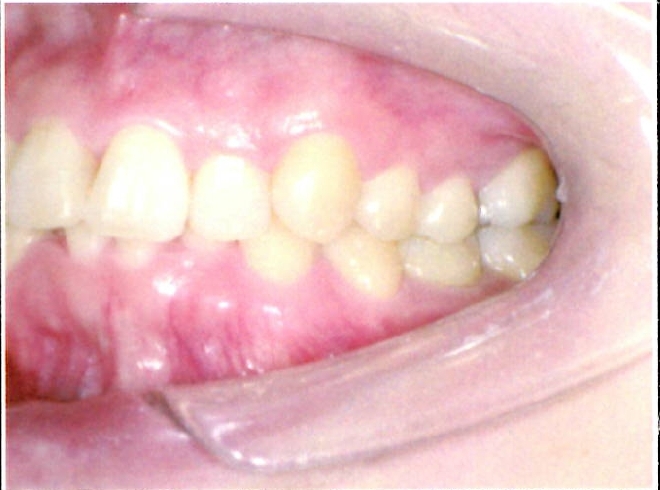

| 主訴・治療前の状態 | 著しい叢生(歯並びのガタガタ)があり、また6歳臼歯(第一大臼歯)が破折していた状態でした。 |

| 治療内容 | 通常の抜歯矯正では第一小臼歯(4番)を抜歯することが多く、その方が治療期間を短縮できますが、小川さんの場合は破折していた6歳臼歯を抜歯し、そのスペースを活用して歯列を整えました。これにより、健康な歯の本数を維持しながら矯正治療を行うことができました。 |

| 治療結果 | 治療前と比較して歯並びが大きく改善し、見た目も大幅に良くなりました。患者様にも大変喜んでいただけた症例です。 |